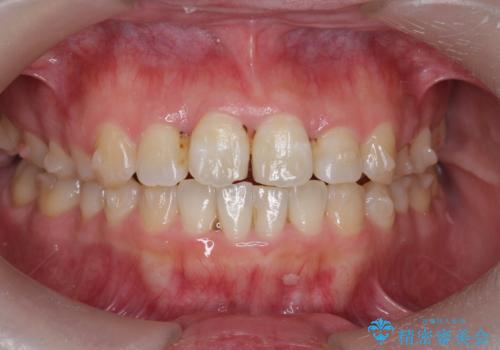

- 前歯のねじれを改善したい、と矯正治療を希望され来院されました。

上下の歯のがたつきを改善するマウスピース矯正治療と、下顎に見られる大きな骨隆起を外科的に除去する治療計画を進めていきます。

歯並びが改善したとともに、骨隆起を除去したことで舌をしまうスペースも増え安定した口腔内環境を確立することができました。